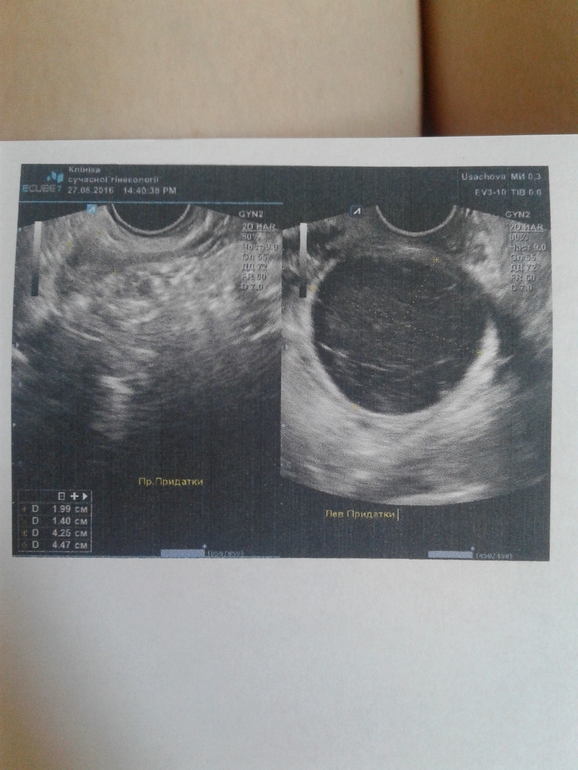

Сегодня была на узи в 15.00. Киста огромная черная на весь экран. 43*46мм (самая большая за 3 года моего "опыта" горького).